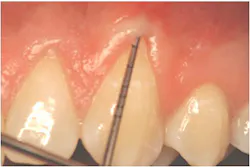

"Recession of the gingiva is becoming a prominent condition in the oral health of many patients and should be treated at its earliest detection," according to A.P. Saadoun in "Current trends in gingival recession coverage - Part I: the tunnel connective tissue graft."5 Saadoun also says the ideal time to correct gingival recession is at a Class I-II, which is less traumatic surgically for the patient, and which achieves predictable regenerative results (see Figures 1, 2).

The A.C.E. starts with marginal tissue evaluation to identify true recession. Using a periodontal probe, take the first measurement from the cemento-enamel junction (CEJ) to the gingival margin on the facial and lingual, and record.